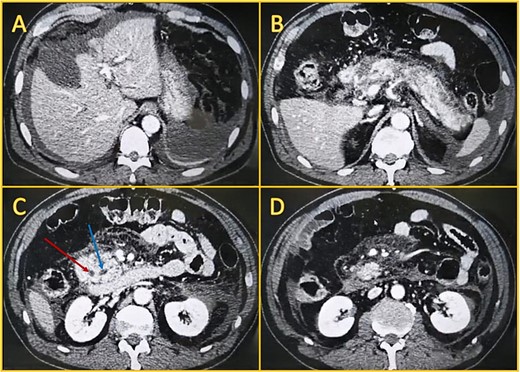

Local complications were suspected, and a contrast-enhanced abdominal computed tomography (CT) was done. It revealed a peripancreatic and perihepatic fluid. The pancreas was enlarged and had several areas of necrosis with gas bubbles (Fig. 1).

Contrast-enhanced computed tomography. A: Perihepatic fluid. B: The pancreatic head, body, and tail have non-enhancing areas compatible with necrosis. C: Dilated biliary duct (leftmost arrow) and Wirsung (rightmost arrow). D: Peripancreatic fluid.